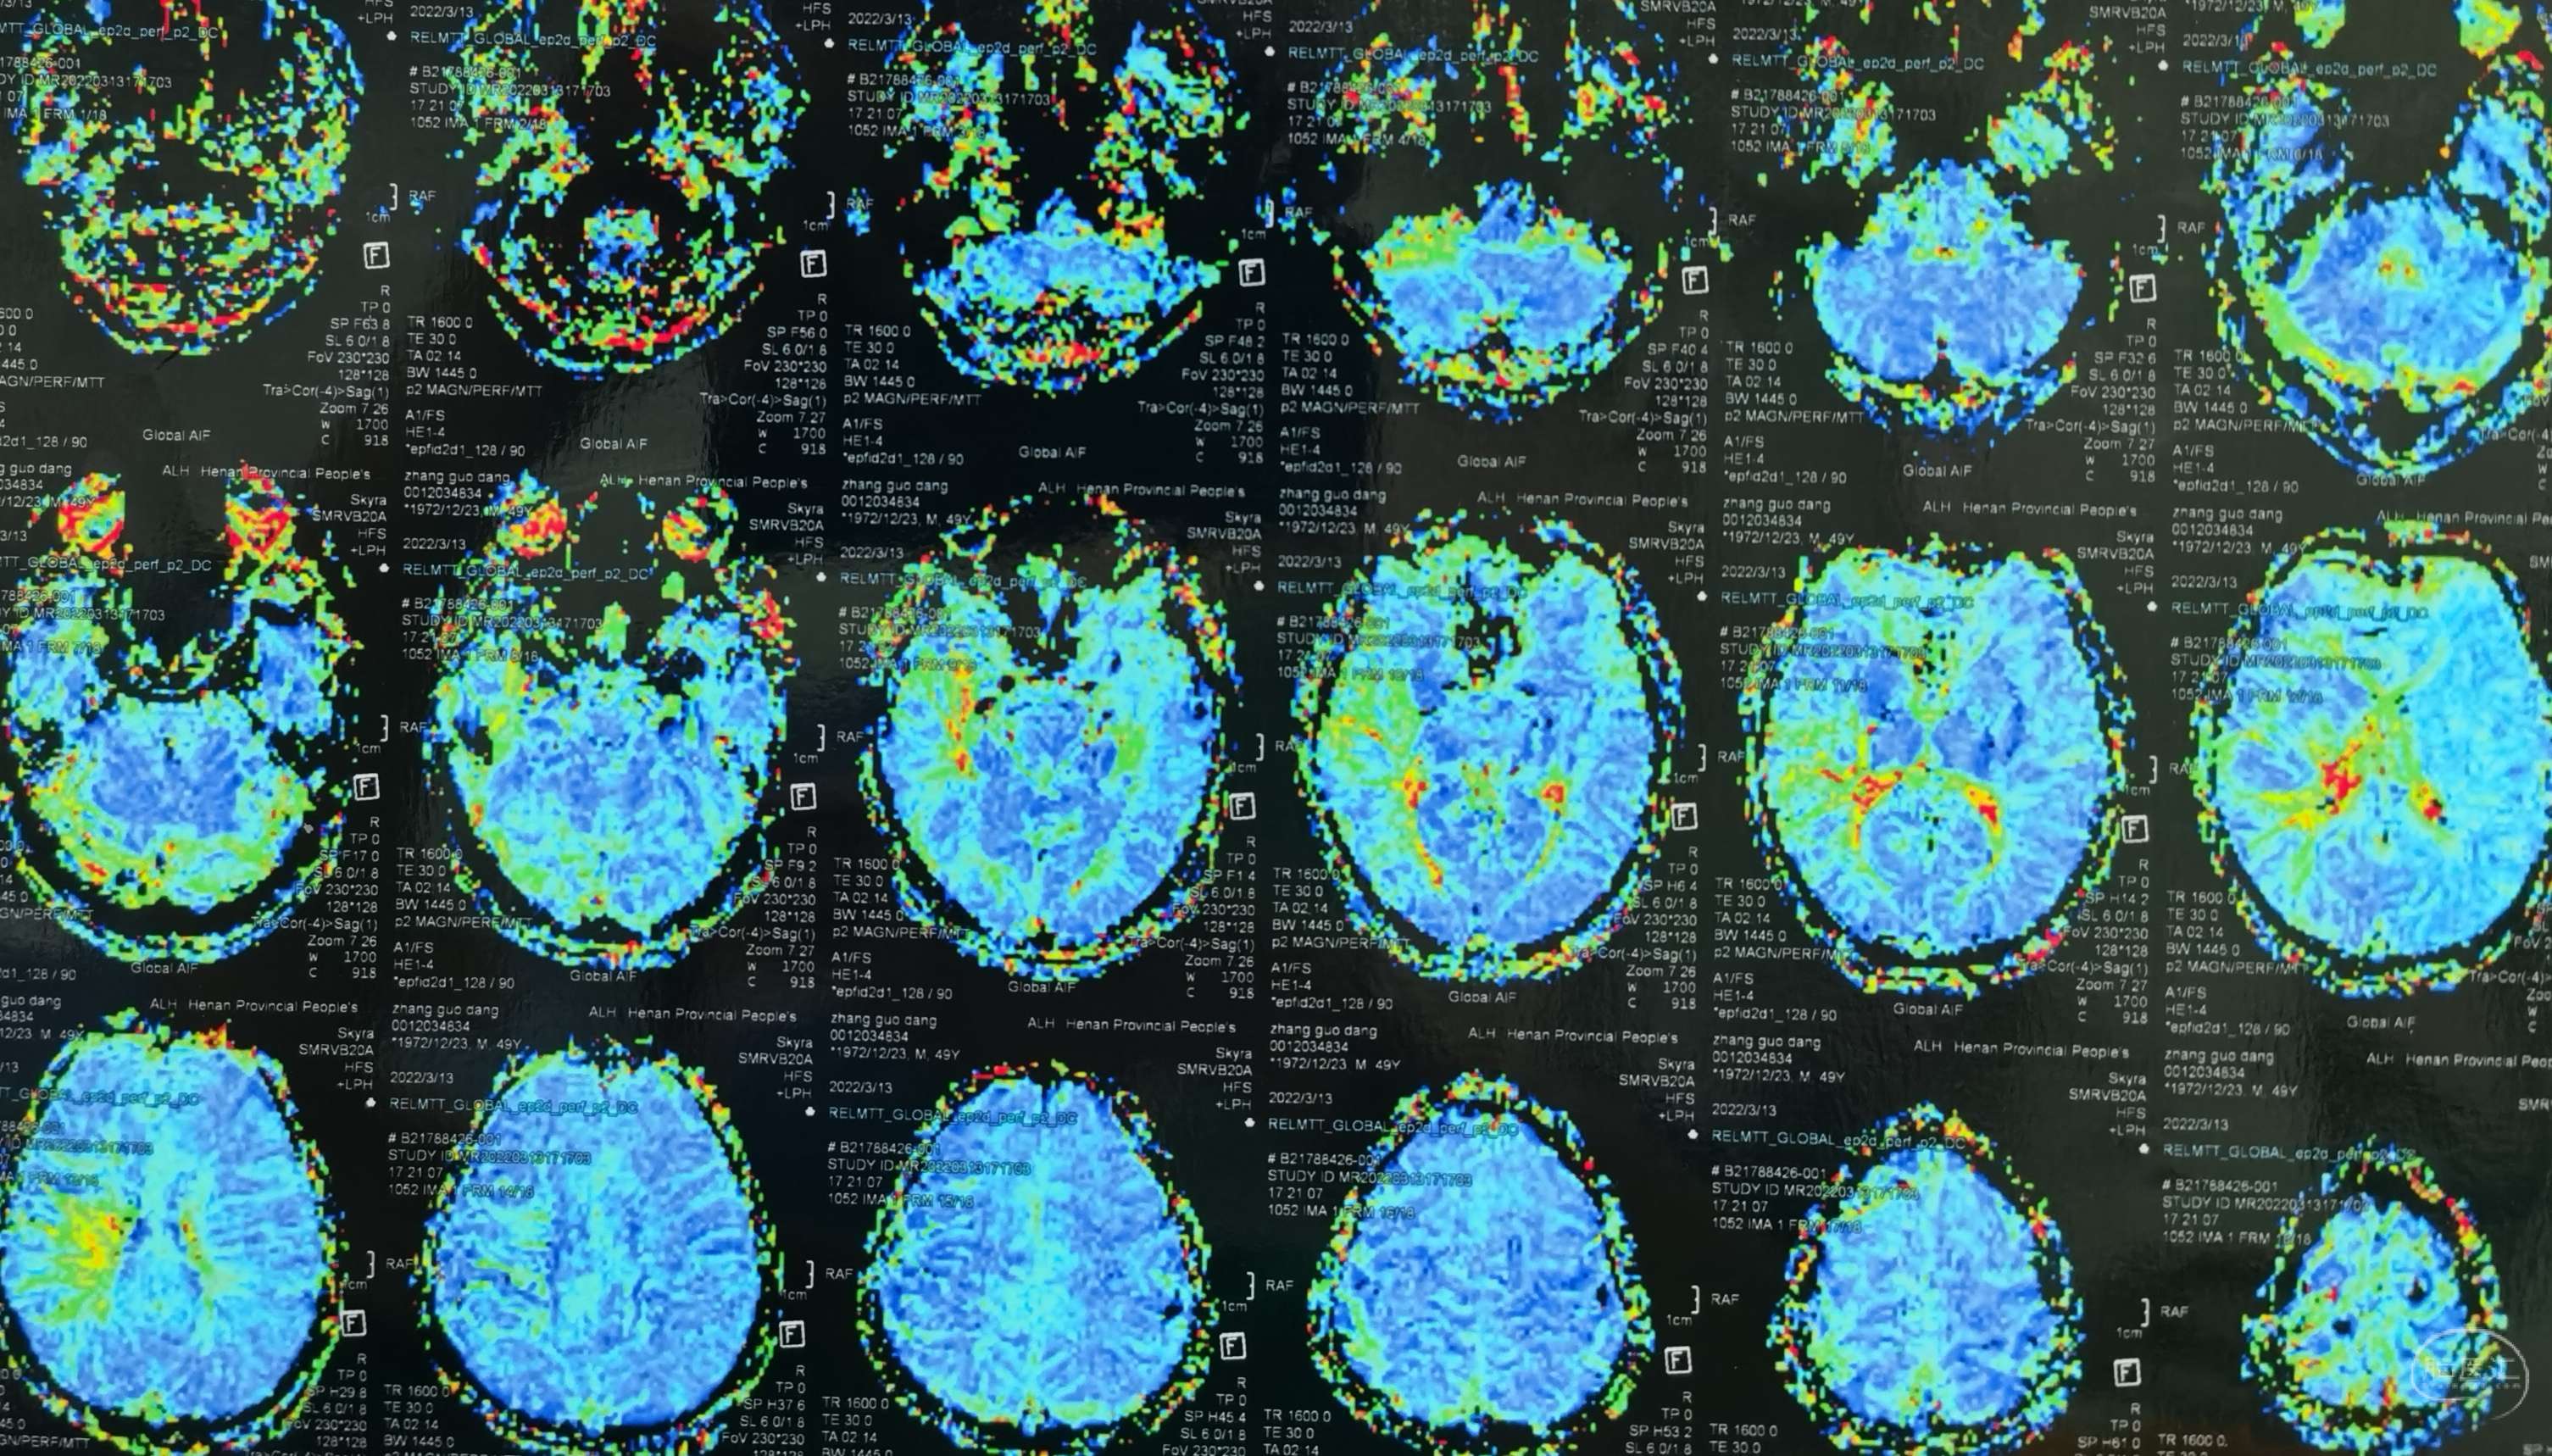

脑灌注提示:左侧大脑半球低灌注缺血。

脑灌注提示:右侧大脑半球低灌注缺血。

脑灌注提示:双侧大脑半球低灌注缺血。

脑灌注提示:双侧大脑半球低灌注缺血。

脑灌注提示:双侧大脑半球低灌注缺血。